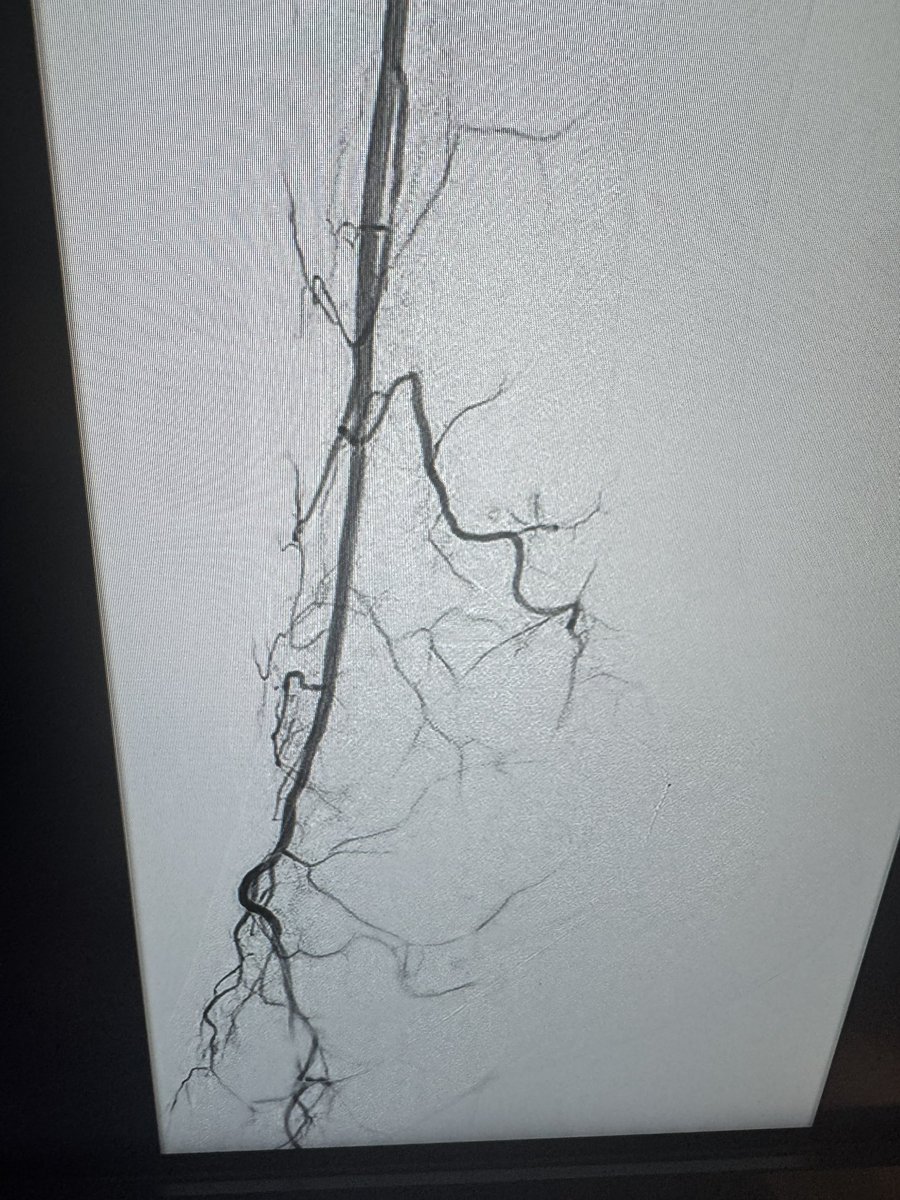

Daniel Burritt Shockwave Medical Leigh Ann O'Banion UCSF Fresno I think what’s important is the patient outcome, not being a lesionologist trying to make the angio look better but improved perfusion to heal a wound. It’s about the patient, not the picture

Leigh Ann O'Banion Dejah Judelson (she/her) Daniel Burritt Viraj Pandit 👊🏾👍🏾BT Fisher Sr., MD Shockwave Medical UCSF Fresno I appreciate Leigh Ann O'Banion for NOT posting a “best case”. Most of us are guilty of Twitter selection bias where we only post dramatic “angio wins”, which distorts efficacy expectations. This procedure improved flow in a calcified artery and promoted healing- nicely done 👍🏻.